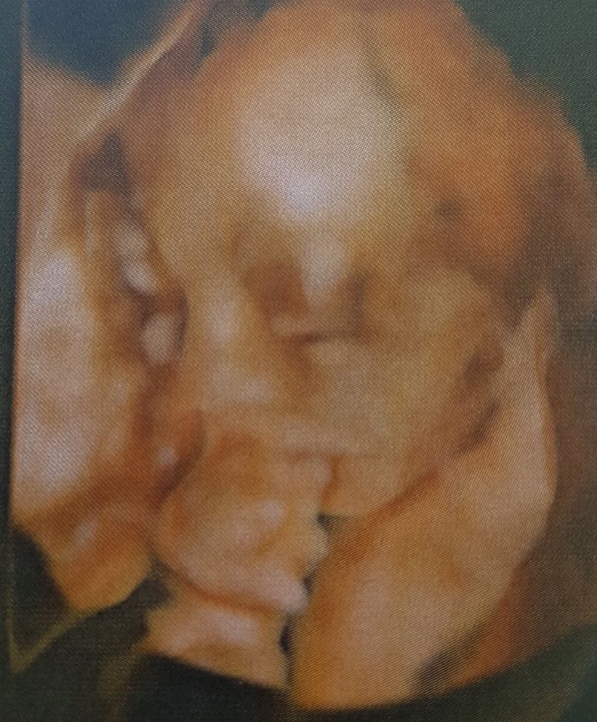

è bravissima questa pupa che si fa sentire per benino

Daniii un mondo di auguri!Che gioia! Sono felicissima per voi, stra felice davvero!un grande abbraccioDaniela72 ha scritto:È arrivata Livia![]()

Mamma e piccola stanno bene.